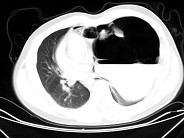

- 单项选择题女,6岁, 胸闷,咳嗽, 胸部CT如图,最可能的诊断为 ( )

A、畸胎瘤

B、右侧液气胸

C、右肺肺大疱

D、右侧脓胸

E、支气管囊肿并感染